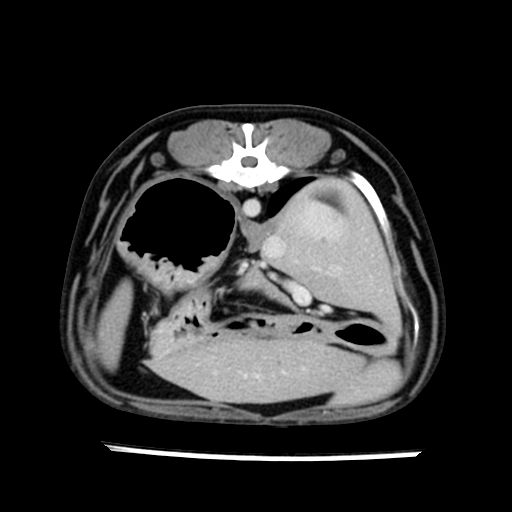

prescritto esame TAC

sequenza immagini limitata al fegato reni e surreni

le immagini ecografiche rispetto alla tac datano circa 7 mesi prima ,le surrenali sono normali nonostante il test acth sia risultato positivo .all’esame TAC dopo diversi mesi risultano aumentate armonicamente nel volume e si individua un forte sospetto di adenoma ipofisario .

sospetto adenoma ipofisario vs. meno probabilmente meningioma della base; intertiziopatia polmonare; lesione espansiva epatica, verosimilmente del lobo laterale sinistro, di sospetta natura neoplastica; lesioni spleniche di natura da definire; iperplasia/ipertrofia delle ghiandole surrenali, bilateralmente; vertebra di transizione del rachide toracico; tenosinovite cronica del muscolo bicipite brachiale di destra.